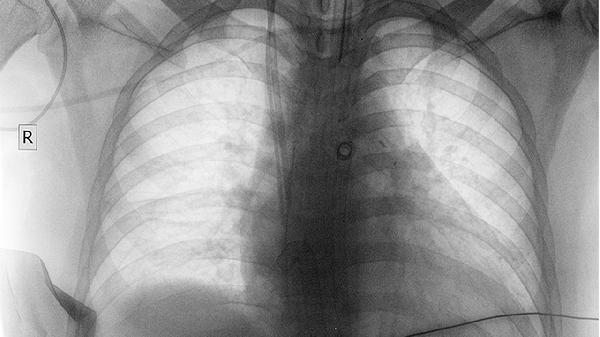

多数正规企业将入职体检列为招聘成本,体检前会提供指定机构名单或发放体检卡。员工需携带身份证原件,按企业要求完成血常规、胸透、肝功能等基础项目。部分外企或大型国企可能覆盖更全面的检查,如心电图、B超等。

体检前三天保持清淡饮食,避免高脂高糖食物影响血糖血脂检测结果。建议选择早晨空腹体检,完成抽血后可适当补充含糖饮品。长期服药者需提前告知高血压患者体检当日应正常服药。女性避开生理期进行尿常规检查,胸片检查前需去除金属饰品。完成体检后保留完整报告原件,部分企业会要求三个月内的体检报告重复使用。